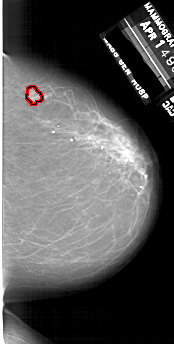

A_1747_1.LEFT_CC

RIGHT_CC LINES 6181 PIXELS_PER_LINE 3121 BITS_PER_PIXEL 12 RESOLUTION 43.5 OVERLAY

FILE: A_1747_1.RIGHT_CC.OVERLAY

TOTAL_ABNORMALITIES 1

ABNORMALITY 1

LESION_TYPE MASS SHAPE LOBULATED MARGINS ILL_DEFINED

ASSESSMENT 4

SUBTLETY 3

PATHOLOGY BENIGN

TOTAL_OUTLINES 1

BOUNDARY